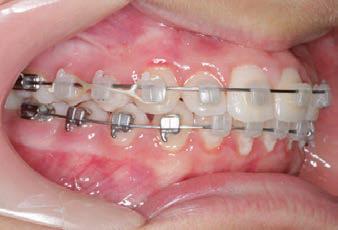

CLASS II DIV.1 - Marra

PROVIDED BY: DR. LUIS CARRIÈRE

INITIAL - 4/4/18

PROGRESS 1 - 26/9/18 - Class I platform accomplished in 5.75 months with Motion 3D COLOR Appliance

PROGRESS 2 - 26/9/18 - Placement of the SLX 3D Clear Brackets

[CONTINUED ON NEXT PAGE]

with M-ONE .015 Cu Nitanium 27°

PROVIDED BY: DR. LUIS

PROGRESS 3 - 30/10/18 - With M-TWO .020 x .020 Cu Nitanium 35° archwire

PROGRESS 4 - 27/11/18 - 3 links power chain: 5, 4, bypass 3 to crimp hooks

PROGRESS 5 - 13/3/19 - With M-TWO .020 x .020 Cu Nitanium 35° archwire

PROGRESS 6 - 1/8/19 - With M-THREE.019 x .025 Beta Titanium wire

52 HENRY SCHEIN ORTHODONTICS

FINAL - 10/10/19 - Appliances removed AFTER

PROGRESS 7 - 10/10/19 - Final day in SLX 3D Clear Brackets BEFORE